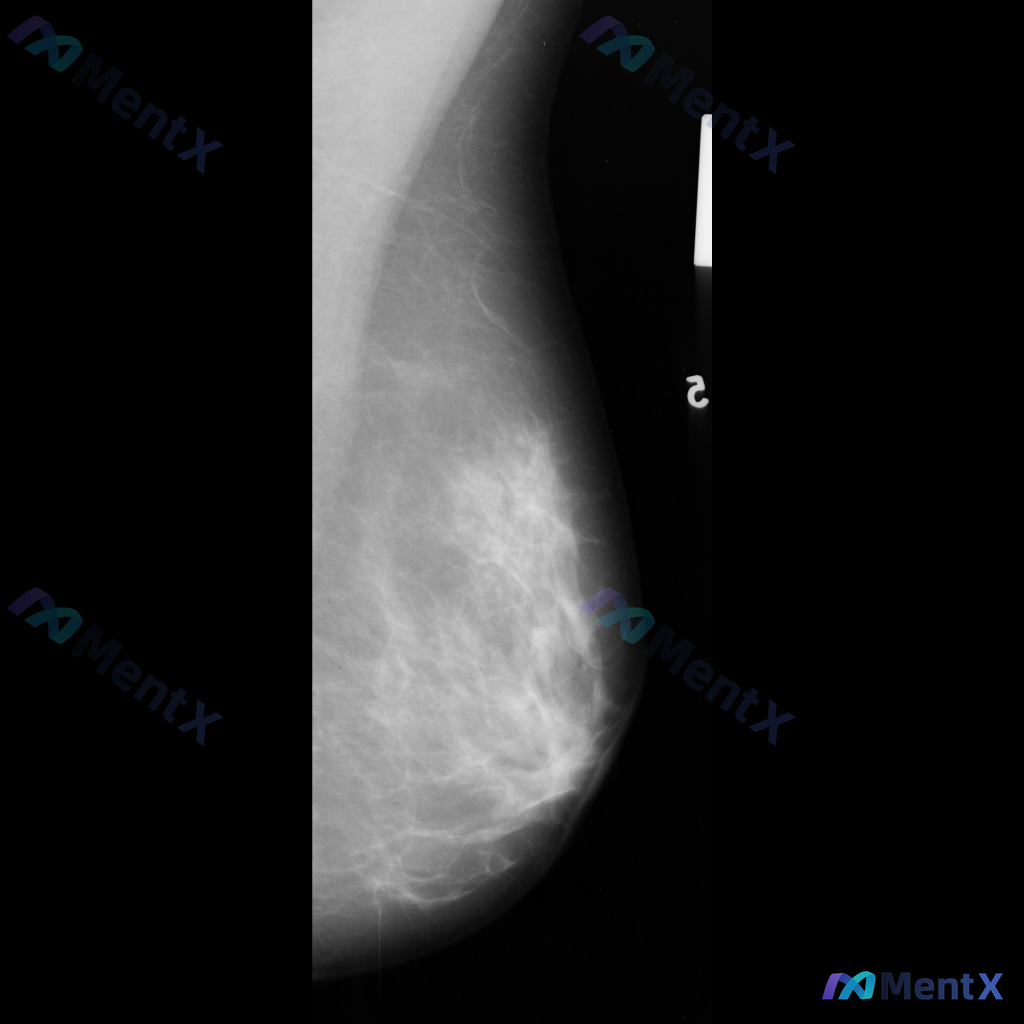

整理到一份乳腺钼靶影像的病例资料,目前只有单侧MLO位片: 影像表现:在乳腺中央偏上方区域可见一个高密度、类圆形的单个钙化影,边界清晰,大小约2-3毫米。目前没有看到明确的肿块、结构扭曲或不对称致密影等其他可疑征象。 想请教大家,单看这组单侧MLO位的影像表现,你会先怎么判断这个钙化的性质倾向?后续...

整理到一份右侧乳腺钼靶的影像资料,先和大家说一下表现: - 背景为不均匀致密型乳腺 - 右侧乳腺中部偏上区域可见局限性、成簇的细小多形性钙化 - 钙化区域周围可见局部密度略增高/结构异常的表现 目前还没有进一步的检查结果,单看这组影像表现,大家会优先往哪个方向考虑?后续评估思路是什么?